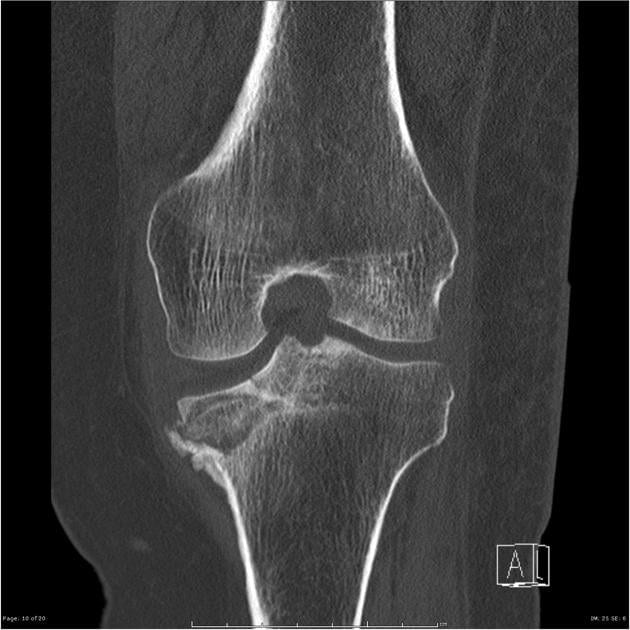

Лечением деформирующего артрита занимаются ревматологи или ортопеды, постравматического — травматологи. Если в штате больницы таких специалистов нет, нужно записаться на прием к терапевту. Первичный диагноз выставляется на основании жалоб пациента, его внешнего осмотра, изучения анамнеза. Для подтверждения проводится ряд инструментальных и лабораторных исследований. Наиболее информативна рентгенография, позволяющая выявить все характерные признаки деформации суставов — субхондральный остеосклероз, сузившуюся щель, сформировавшиеся кисты и остеофиты.

Для оценки состояния соединительнотканных структур (связок, сухожилий, мышц) проводится МРТ или КТ. При тяжелом течении артрита пациентам показана артроскопия. В полость сустава вводится устройство, оснащенное миниатюрной видеокамерой. Во время ее продвижения изображение внутренней поверхности сочленения передается на монитор. Во время артроскопии проводится забор синовиальной жидкости для изучения ее состава. При необходимости берутся биоптаты синовиальной оболочки и хрящевых тканей.

Для деформирующего артрита любой локализации характерны такие клинические и рентгенологические признаки:

- ограничение подвижности сочленений из-за уменьшения размеров суставных щелей;

- разрастание остеофитов, провоцирующее развитие синовита и воспаление мягких тканей;

- необратимая деформация крупных и мелких суставов в результате дегенерации субхондральных костей;

| Третья | На рентгенологических изображениях заметно полное или частичное сращение суставных щелей и множество сформировавшихся крупных остеофитов около сочленений. Артралгия становится постоянной, усиливается при малейшем движении. Суставы тугоподвижны в течение всего дня из-за развившегося анкилоза. Консервативное лечение не эффективно, направлено только на устранение болей. Пациента готовят к хирургическому вмешательству — корригирующей остеотомии, но чаще к эндопротезированию |